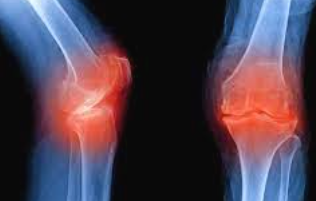

무릎 연골 손상은 현대인에게 매우 흔한 질환으로, 초기 증상을 놓치면 심각한 관절염으로 발전할 수 있습니다. 본 가이드에서는 무릎 연골 손상의 다양한 증상과 단계별 특징을 상세히 알아보겠습니다.

무릎 연골 손상의 가장 대표적인 증상은 무릎 관절 부위의 통증입니다. 초기에는 운동 후나 장시간 활동 후에만 나타나지만, 손상이 진행되면서 일상적인 움직임에서도 통증이 발생합니다. 특히 계단을 오르내리거나 쪼그려 앉는 동작에서 통증이 심화되는 특징을 보입니다.

연골 손상으로 인한 통증은 날카로운 찌르는 듯한 통증보다는 둔하고 깊은 곳에서 느껴지는 통증의 양상을 보입니다. 무릎을 직접 눌렀을 때 압통이 느껴지며, 특히 무릎뼈 주변과 관절선 부위에서 압통이 두드러집니다.

무릎 연골 손상이 진행되면 결국 퇴행성 관절염으로 발전하게 됩니다. 초기 연골 손상 증상이 관절염의 전단계 증상으로 볼 수 있으며, 조기 발견과 치료가 관절염 예방에 매우 중요합니다.